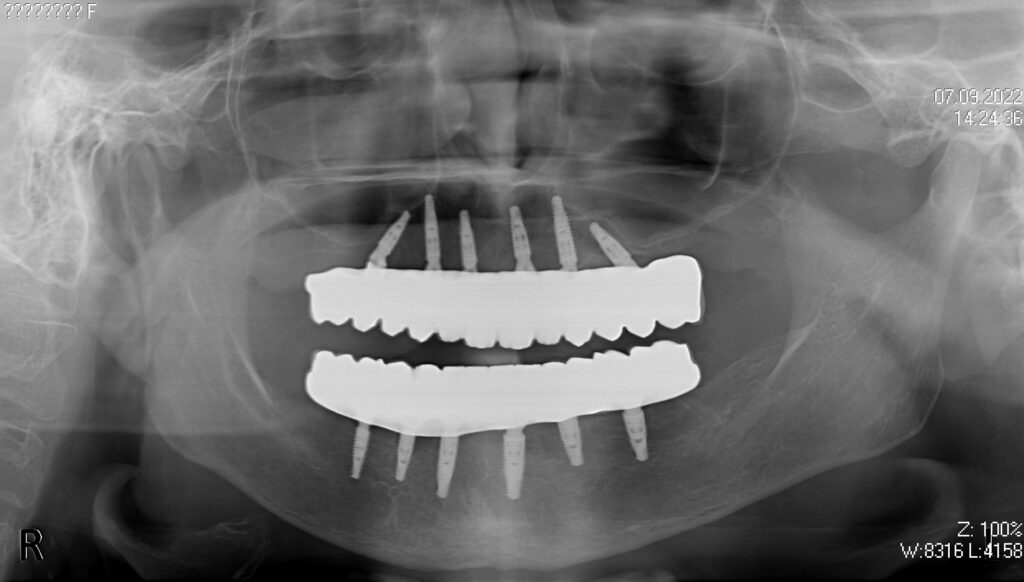

Пациент продолжает лечение спустя 6 месяцев после имплантации и установки временных металлоакриловых протезов с опорой на 6-ти дентальных имплантантах на каждой челюсти.

Диагноз: Полная адентия нижней и верхней челюстей.

снимок